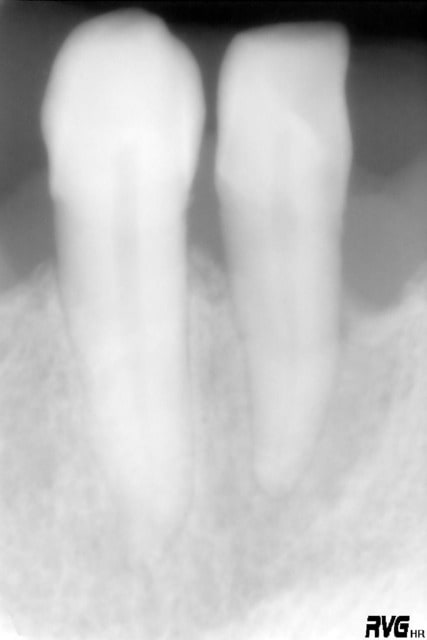

tiens je mets un second cas en mligne avant après et tu me diras ce qyue représente la petite image residuelle en mésial ....canal latéral ?

phil

19/09/2005 à 23h23

voici donc ce second cas ....